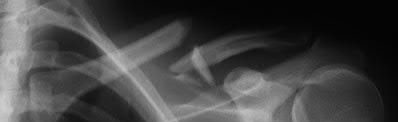

Figure A shows a radiograph of a 19-year-old male with an isolated shotgun injury. On physical examination, he has a 3 cm wound over the posterolateral aspect of his arm. In addition, he has weakness with wrist and finger extension, but no sensory deficits. The patient has received tetanus prophylaxis and antibiotics in the emergency department. What would be the next best steps in treatment?

This patient has sustained a shotgun blast to the midshaft humerus. The next best step would be irrigation and debridement, and external fixation of the fracture.

Shotgun injuries are typically treated as open fractures, whereas low-energy gunshot wounds are treated as closed fractures. The initial operative treatment of shotgun wounds should include irrigation and debridement and stabilization with external fixation. The goal of treatment is to stabilize the severe soft-tissue injury and bone loss, as well as to aggressively debride devitalized tissue and gross contamination.

Dougherty et al. reviewed gunshot fractures to the humerus. They report that

peripheral nerve injuries are relatively common with these injuries, with a more common incidence in distal injuries than proximal.

Joshi et al. looked at low velocity gunshot fractures to the humerus. They found that these injuries can be safely treated as closed fractures with local wound care, fracture brace and oral antibiotics. The time to union was similar in the non-operative and open treatment group.

Berick et al. examined the indications for nerve exploration with humerus gunshot fractures. They recommend continued observation of isolated nerve palsies associated with gunshot fractures of the humerus. However, consider early nerve exploration of palsies when associated with a concomitant vascular injury.

Figure A shows a high velocity shotgun fracture to the left humerus with retained buck fragments. Illustration A shows a similar injury stabilized with external fixation.

Incorrect Answers:

Answer 1: Due to the severity of soft tissue injury, external fixation should be considered for initial stabilization. Vascularized fibular grafts has been expanded to an osteoseptocutaneous flap by including a cutaneous flap on the lateral aspect of the lower leg. These are not typically used in the acute setting.

Answer 3: Retrograde intramedullary nail would not be the ideal implant for this injury, acutely.

Answer 4 and 5: There is no indication for a CT scan or prolonged antibiotics. The fracture and soft-tissue injury should be initially stabilized with external fixation. Coaptation splinting will interfere with soft tissue care.